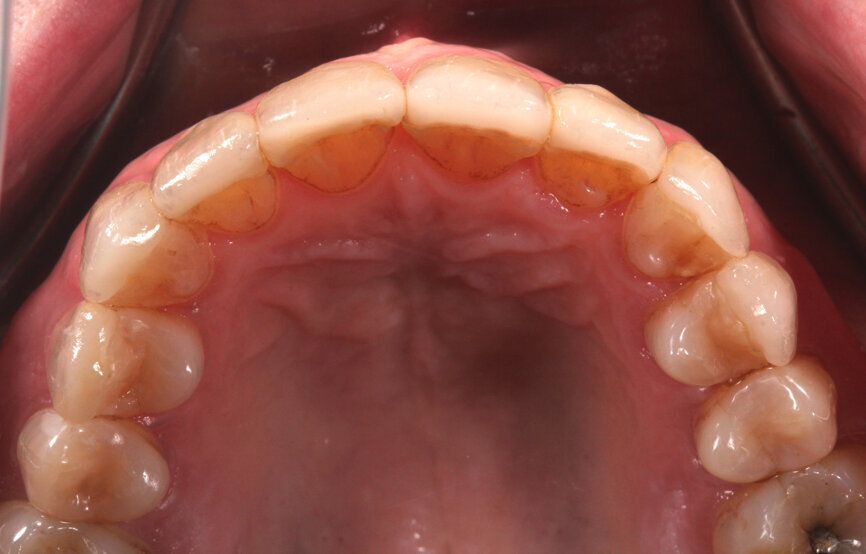

Fig. 13: Preoperative intra-oral photograph.

A 62-year-old woman presented to the Comprehensive Care Clinic at the Dental College of Georgia at Augusta University, Augusta, Georgia, US, with the chief complaint of worn and stained anterior teeth (Figs. 12 & 13). The patient was a smoker and reportedly smoked a pack per week.